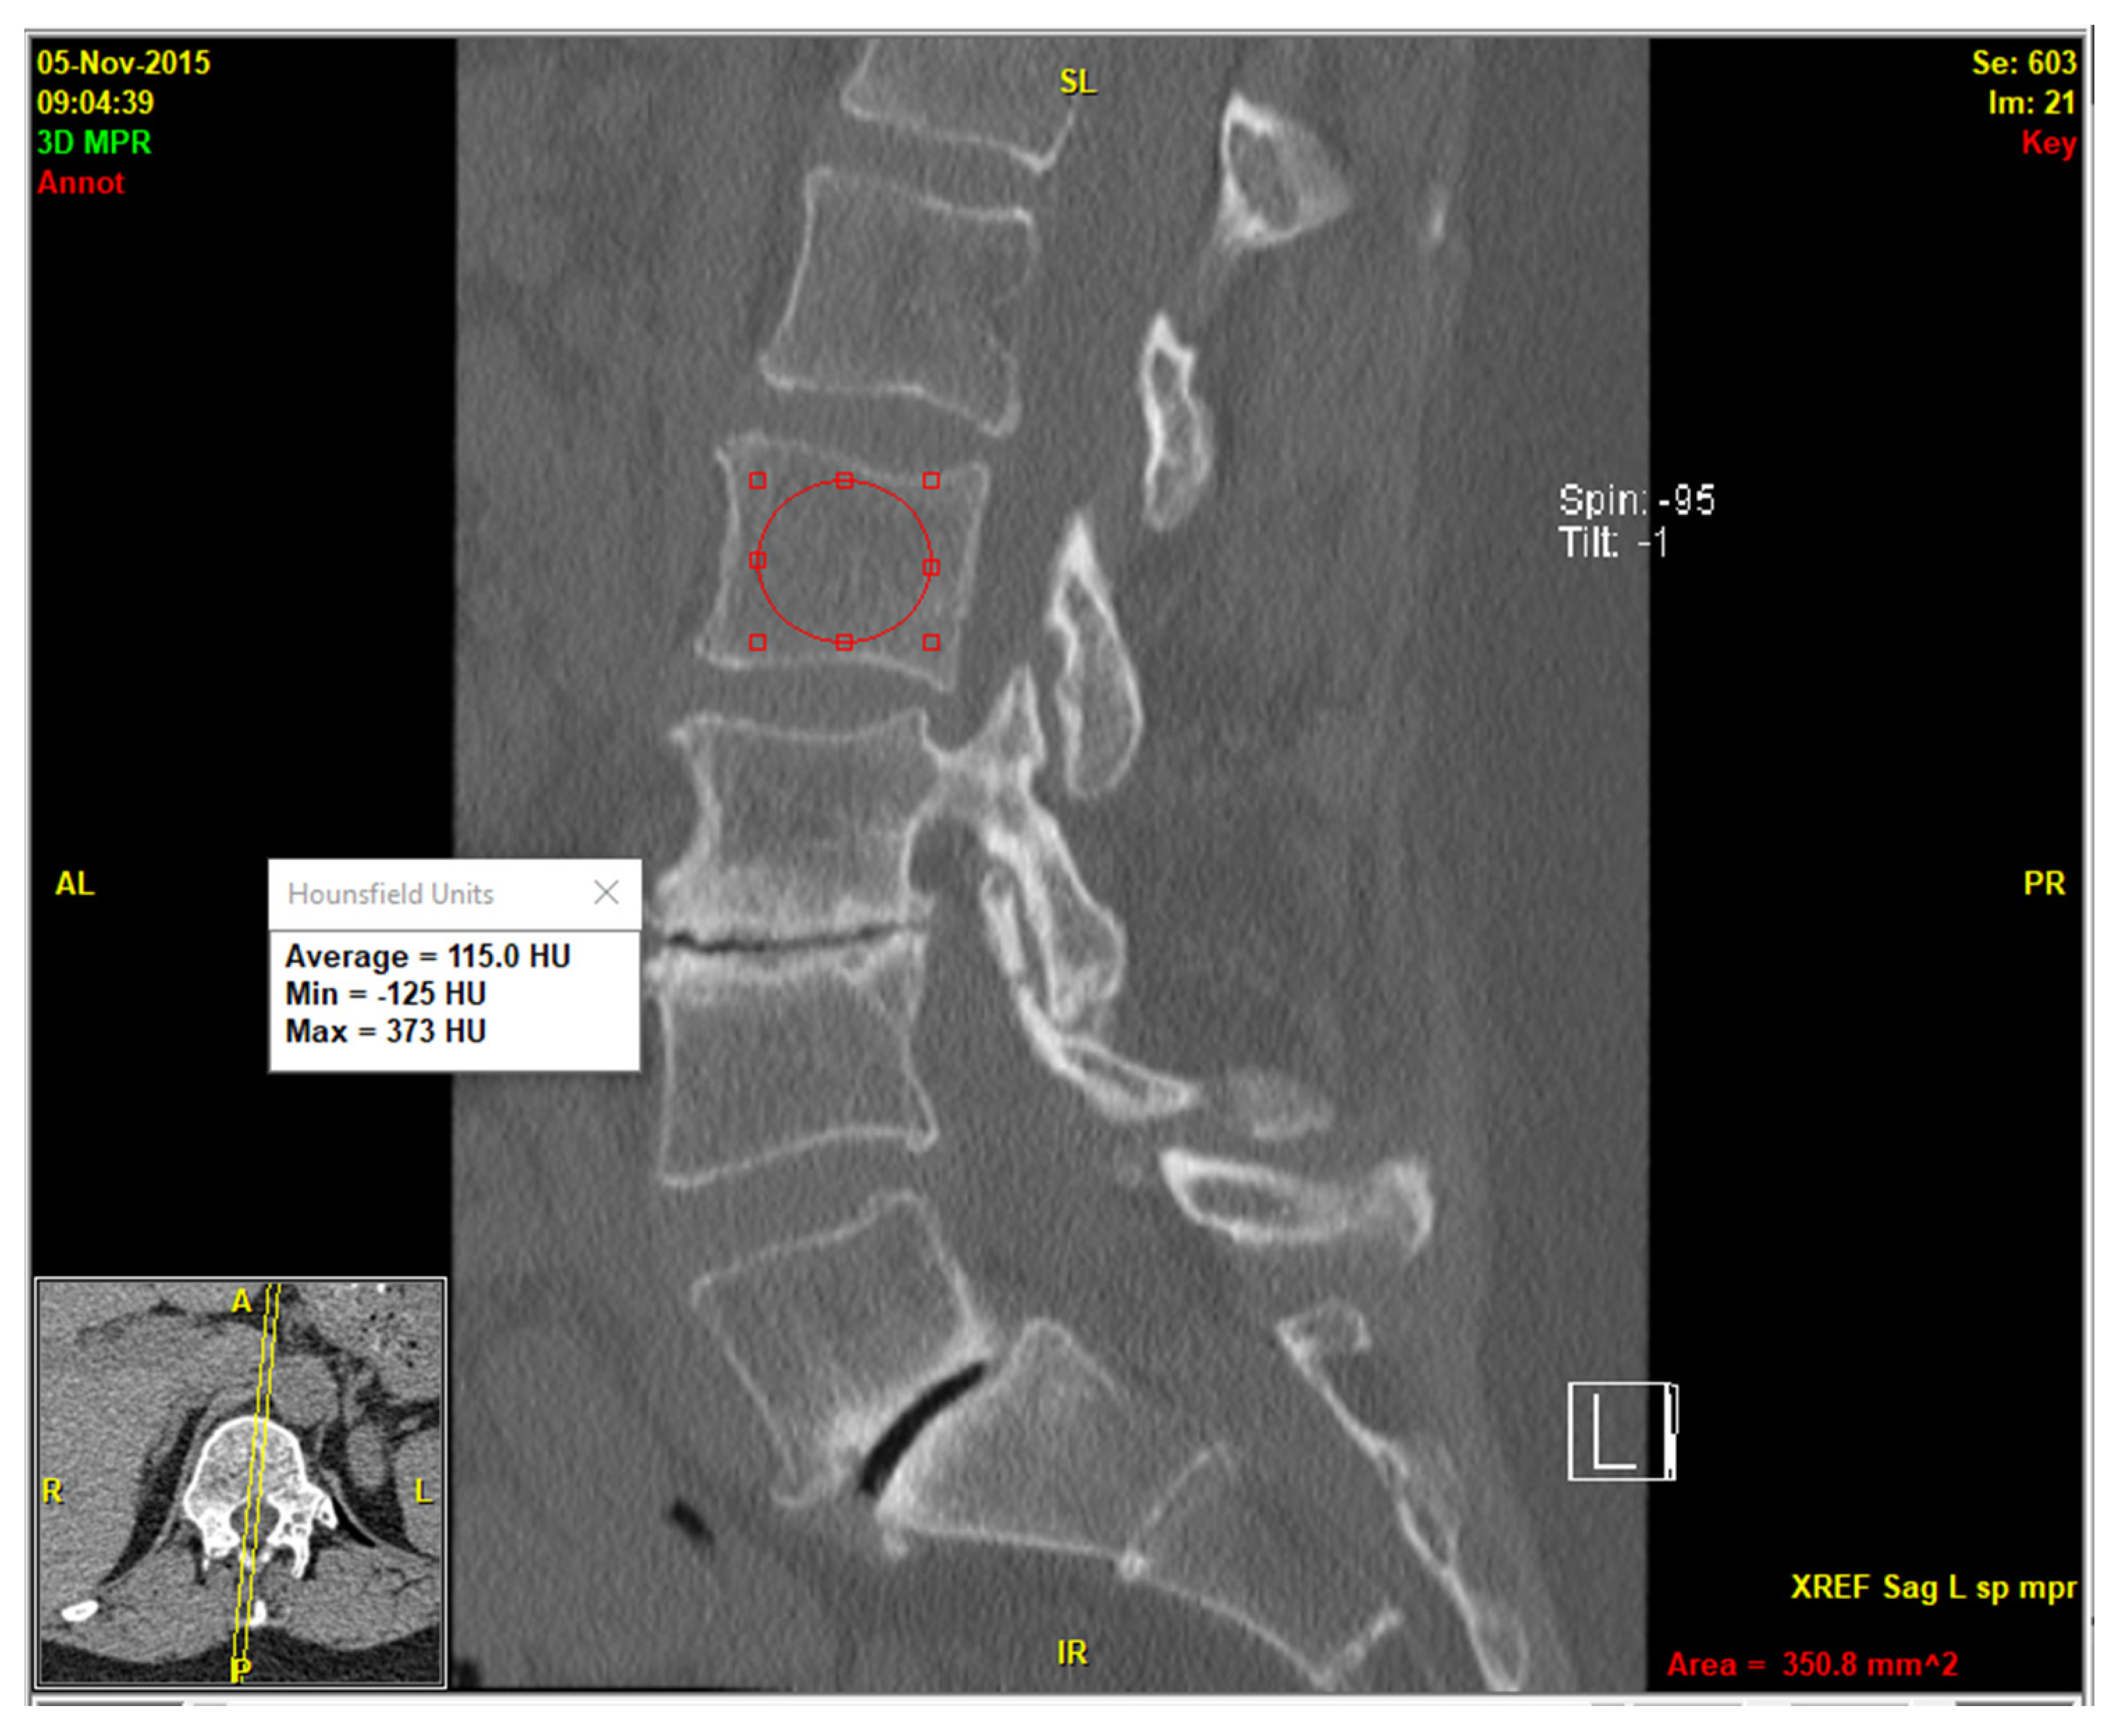

A recently developed deep-reasoning and learning-based model (DR-AI; Deep Reasoning AI Inc., Ithaca, NY, USA) was employed to automate vertebral segmentation and volumetric HU quantification of the cancellous part of the vertebrae, excluding the cortical parts and all possible osteophytes, which may lead to false-negative diagnosis. The model was developed based on publicly available data (deepreasoning3d.com) as well as deidentified patients’ data from our institution. This was performed by an imaging technologist and a research coordinator according to HIPAA guidelines [15]. It integrated deep learning for pattern recognition with reasoning capabilities to solve complex segmentation tasks in an unsupervised or weakly supervised manner [16]. Leveraging an open-source framework for the automated vertebral segmentation [11], it was trained on a dataset of CT scans with annotated vertebral labels (Figure 1). To evaluate the reliability of the automated volumetric HU measurements, random spot checks were performed on a mid-sagittal slice of the CT series using clinical image viewer software (QReads 5.15.3).

A total of 84 patients (67 females and 17 males) met the inclusion and exclusion criteria. All patients were Caucasian, and mean age at imaging was 74.1 ± 10.3 years for females and 68.1 ± 12.4 years for males. The deep-reasoning and learning-based model (DR-AI) successfully demonstrated robust performance in segmenting and quantifying volumetric HU for all L1–L4 vertebrae with high fidelity. Random spot checks confirmed accurate delineation of vertebral boundaries, with no significant discrepancies between automated and manual measurements on mid-sagittal slices (Figure 2). The model processed each CT scan in approximately 30.4 s when hosted on an A100 NVIDIA GPU, (NVIDIA Corp., Santa Clara, CA, USA) providing both the volumetric HU and volume for all scanned vertebrae from all available kernels (Figure 3).

Figure 2. Conventional mid-sagittal method of opportunistic HU measurement.